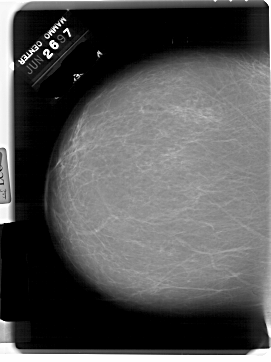

A_1796_1.RIGHT_MLO

RIGHT_MLO LINES 6871 PIXELS_PER_LINE 4336 BITS_PER_PIXEL 12 RESOLUTION 43.5 OVERLAY

FILE: A_1796_1.RIGHT_MLO.OVERLAY

TOTAL_ABNORMALITIES 1

ABNORMALITY 1

LESION_TYPE MASS SHAPE IRREGULAR MARGINS ILL_DEFINED

ASSESSMENT 4

SUBTLETY 5

PATHOLOGY BENIGN